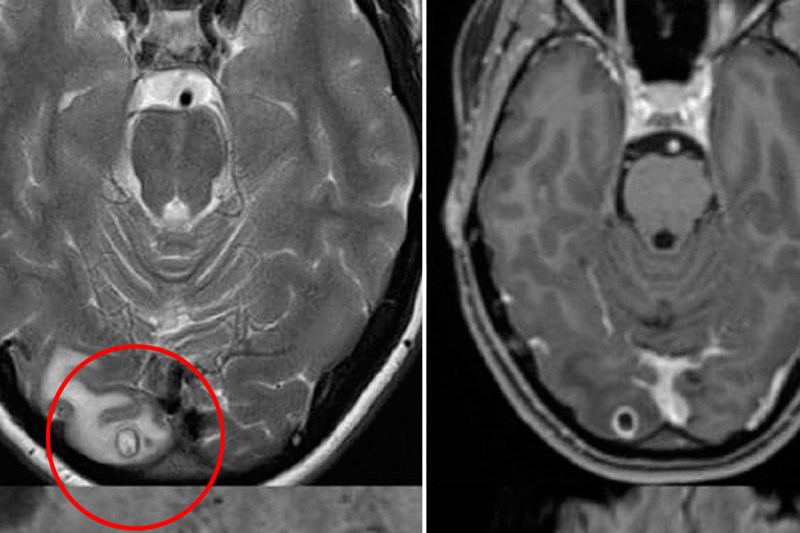

दिमाग में कीड़ा होने के लक्षण

- लगातार या अचानक सिर में दर्द होना सिर में अचानक तेज़ दर्द या लगातार बिना किसी ओर वजह के दर्द होना।

- मिचली या उल्टी का आना।

- दिखाई देने में मुश्किल होना।

- शरीर का तालमेल बैठाने में दिक्कत।

ये प्रारंभिक लक्षण हैं दिमाग में टैमवर्म के पहुंचे के।